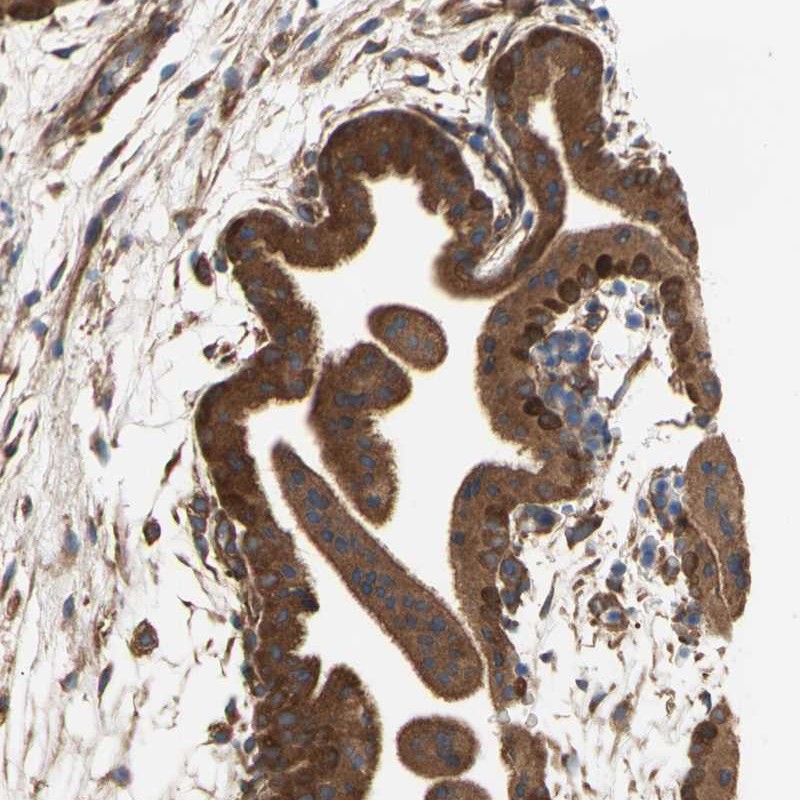

Supportive validation

- Experimental details

- Immunohistochemical staining of human placenta shows strong cytoplasmic positivity in trophoblastic cells.

- Validation comment

- Staining pattern consistent with experimental and/or bioinformatic data.